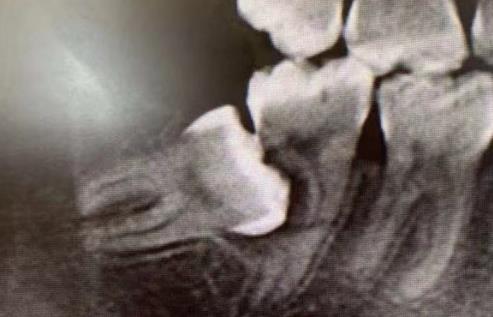

7、有沒有長智齒?是否經常發炎?智齒是從(cong) 門牙往後數的第8顆牙,有的肉眼可見,有的需要拍片確定。如果有,建議盡早確定要不要拔除,因為(wei) 大部分智齒可能要拔。

智齒連累鄰牙壞掉